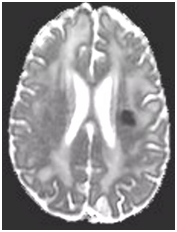

During follow-up in stroke clinic, her imaging was reviewed. MR imaging demonstrated large confluent areas of hyperintense T2 and FLAIR signal abnormality throughout the periventricular and deep white matter with extension into the subcortical white matter (Figure 1) (Figure 2). T1w images demonstrated low signal, corresponding to the T2/FLAIR abnormality on T2w images. This white matter abnormality is known as leukoaraiosis. The hyperintense T2/FLAIR signal abnormality also involved the anterior temporal lobes (Figure 3) (Figure 4) and external capsules (Figure 5) (Figure 6). This feature on MRI is uncharacteristic of other white matter diseases, notably the sporadic subcortical atherosclerotic encephalopathy. In our patient, the corpus callosum was spared. The lacunar infarcts were small vessel infarcts, typically seen in the deep white matter, basal ganglia, thalami, and the pons. On diffusion images, there was a small area of diffusion restriction in the left corona radiata that was consistent with an acute infarct (Figure 7) (Figure 8). Subsequently, there was an area of encephalomalacia on follow-up MRI at the location of the previous acute infarct. This abnormality correlated with the right-sided weakness seen prior to the index patient’s admission.

Figure 1 T2w axial image at the level of corona radiata demonstrates confluent hyperintense signal abnormality in the deep and subcortical cerebral white matter.